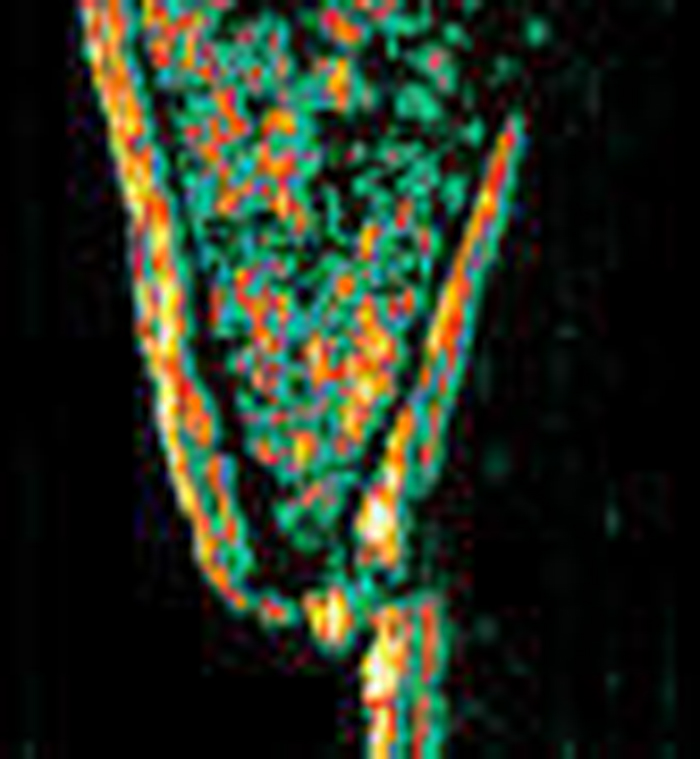

20 MHz 2D images

20 MHz 3D images

| Misc. |  Cellulite, arm |

Microdialysis tube |

Intradermal nevus |

Highlight. intrad. nevus |

| Misc. |  Ageband, forearm |

Nevus, skin parallel cut |

Normal, overlying hairs |